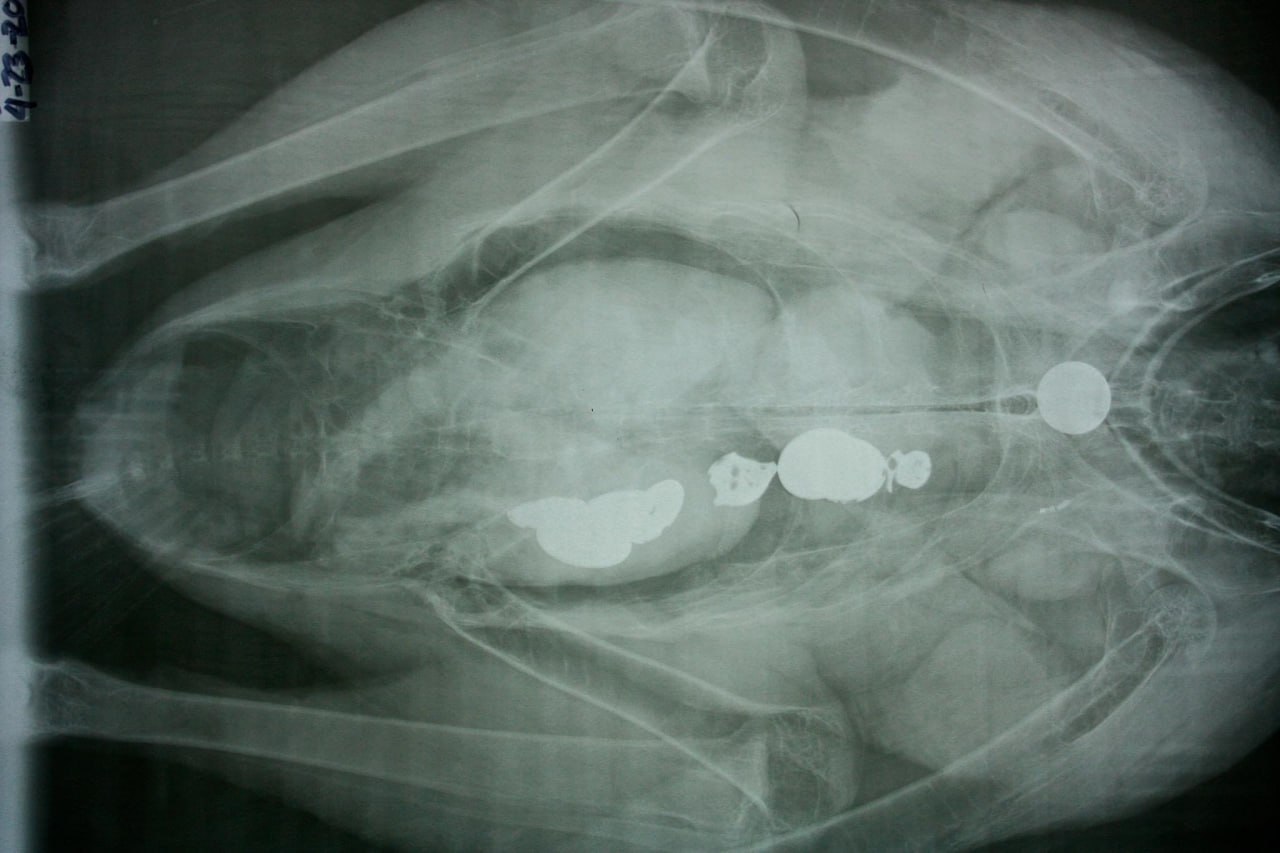

Ảnh X – quang của một con chim nuốt phải chìa khóa từ ổ khóa tình yêu (Nguồn: Fanpage Grand Canyon National Park)

“Condors are curious animails and much like a small child will investigate strange things they come across with their mouths. Condors are not meant to digest metal and many times cannot pass these objects. If a condor ingests too many objects like this, it could die.” (Tạm dịch: Chim ưng là một loài động vật tò mò như một đứa trẻ nhỏ, chúng sẽ khám phá điều mới lạ bằng chiếc mỏ. Cơ thể chúng không có khả năng tiêu hóa kim loại và thường bị mắc nghẹn vì nó. Nếu một con chim ứng ăn quá nhiều thứ như thế, nó sẽ chết), trích bài đăng của Grand Canyon National Park.